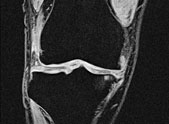

Wir setzen die Magnetresonanztomographie bevorzugt ein bei der Untersuchung von Kindern, bei okkulten Frakturen, ossärer Tumorinfiltration, bei Muskel-, Knorpel- und Bänderverletzungen, in der Gelenk- und der rheumatologischen Diagnostik.

Die Magnetresonanztomographie bietet bei der Untersuchung von funktional differenzierbaren Erkrankungen oder röntgenindifferenten Strukturen Vorteile.

Film: Flüssigkeitsablagerung

im Knie

Film: Kniegelenksathrose

(Zum Abspielen bitte anklicken)